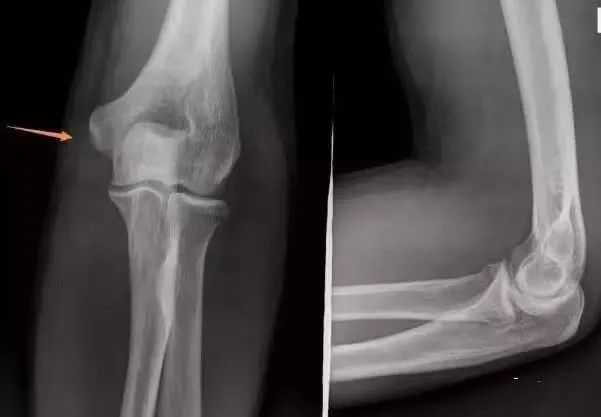

(6)肱骨髁上骨折

肱骨外髁骨折:肿胀及压痛局限于肘外侧,有时可触及骨折块;X片摄片桡骨纵轴线不通过肱骨小头骨化中心。

肱骨髁上骨折:肿痛较明显,呈环周压痛;X线片示骨折线不波及关节面,桡骨纵轴线通过肱骨小头骨化中心。

肱骨小头骨折:单纯的肱骨小头骨折多见于成人,合并部分外髁的肱骨小头骨折以儿童多见。亦有肘外侧及肘部的肿胀、疼痛,功能障碍;肘关节伸屈活动受限,尤其屈曲90-100°,常发生肘部疼痛加重并有阻力感觉;X线表现常有特征性,需仔细观察正、侧位X线片。

(8)肱骨内上髁骨折肘关节后脱位:两者均有肘部疼痛、肿胀,伸直位固定。但脱位为环击肿痛,弹性固定于135°、肘窝可扪及肱骨远端,鹰嘴上方空虚,肘部呈靴状畸形;X线片示脱位、无骨折征。关节向后内或后外脱位,肱骨内上髁骨折常可合并肘关节向后内或后外脱位。